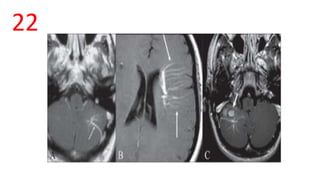

MEDUSA HEAD SIGN/ SPOKE-WHEEL SIGN

• Seen best on Contrast T1 W images.

• Seen in developmental venous anomalies (venous angioma)

MEDUSA HEAD SIGN/SPOKE-WHEEL SIGN • Seen best on Contrast T1 W images. • Seen in developmental venous anomalies (venous angioma)